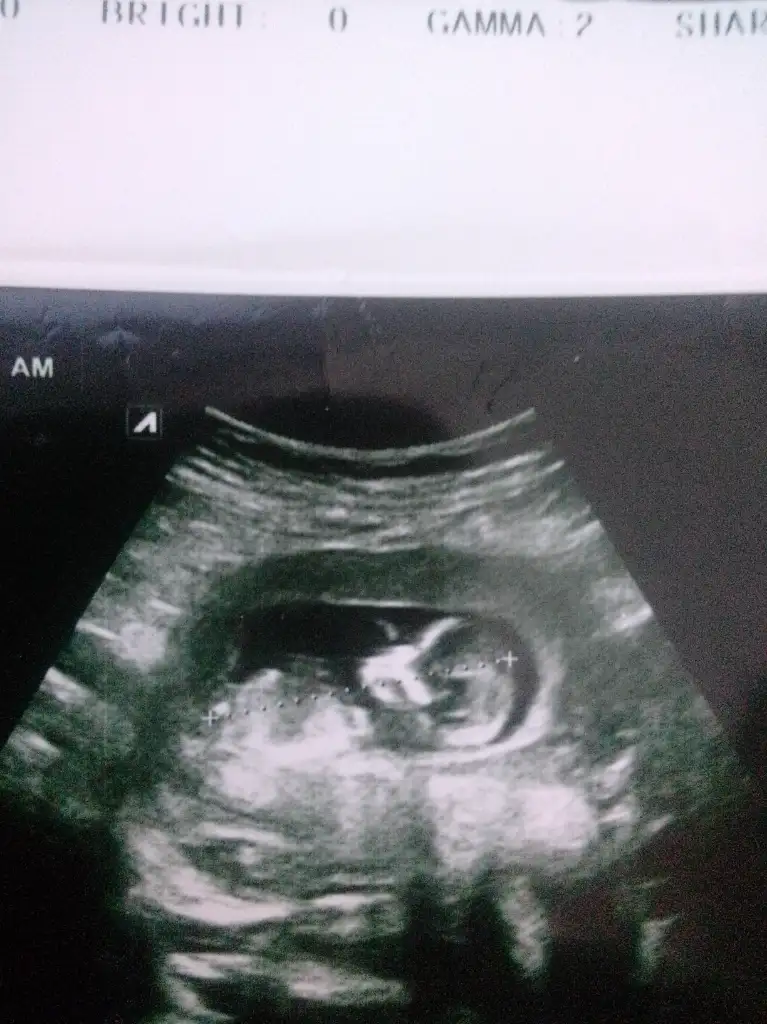

kızKızlar bana da bakar mısınız?? 13 haftalık

çok küçük ama kese kız gibiBana da yorum yapar mısınız 8 haftalık vajinal bakıldı

Ayy insallah ağzınız bal yesinçok küçük ama kese kız gibi